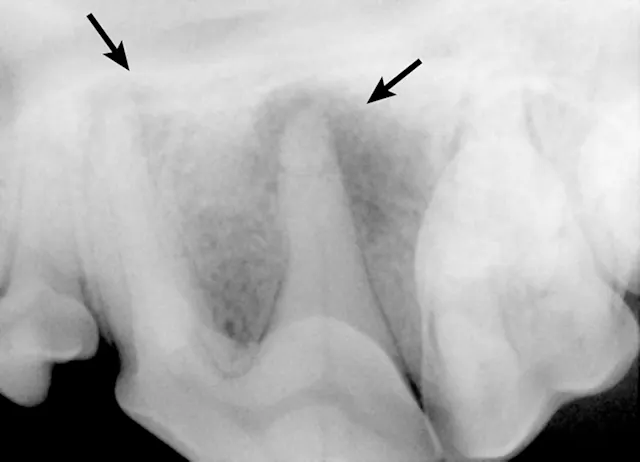

Dental radiography can be used to evaluate tooth structure anomalies and root pathology and to assess pulp canal size. Assessment of pulp canal size can be particularly useful for diagnosing nonvital teeth. A common misconception is that after a tooth dies, the canal becomes uniformly wider. In reality, the canal appears wider as compared with other canals because it stopped producing dentin at the time it became nonvital (Figure 7). Vital teeth with intact pulp have odontoblasts that will continue to produce secondary dentin, causing the pulp chamber to continue to narrow.4 Presence of periapical lucencies (Figure 8) and root resorption on dental radiographs are other indicators that a tooth is nonvital.

If the insult to the tooth happened recently, the pulp chamber size will be the same as the contralateral tooth. Repeat radiographs in 6 months may show that the pulp chambers of vital teeth will continue to narrow and the nonvital tooth pulp chamber will appear larger. Of note, it can be difficult to evaluate subtle changes in canal size in mature dogs with narrow canals.

The pulp chamber of the left mandibular canine (arrows) is significantly wider than the right (arrowheads), indicating that the pulp is no longer producing secondary dentin and is nonvital. Although this is a definitive sign of nonvitality, its absence does not confirm vitality.